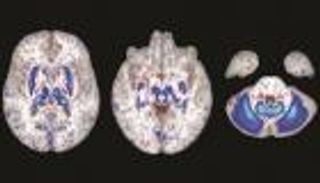

ويتسبب التهاب العضلات العظمي المتقدم في تحول الأنسجة الرخوة، مثل العضلات والأنسجة الضامة، إلى عظام بسبب الطفرة في جين ACVR1، حيث يتحكم هذا الجين في نمو العظام، وعند حدوث خلل فيه، تتشكل العظام في أماكن غير طبيعية خارج الهيكل العظمي المعتاد، وهو ما يعرف بـ "التعظم خارج الهيكل"، و هذا التحول يعرقل الحركة تدريجيا ويؤدي إلى قيود شديدة على مرونة الجسم مع تقدم العمر.

وتشمل المضاعفات الرئيسية للمرض في فقدان تدريجي للحركة، حيث تبدأ العظام الجديدة في تثبيت المفاصل، مما يؤدي إلى صعوبة في الحركة اليومية، في مراحل متقدمة من المرض، يمكن أن يؤثر تكون العظام على مناطق حساسة القفص الصدري، مما يقيد حركة الرئتين ويؤثر على التنفس، وحول الفك والوجه، بما يمكن أن تؤثر على القدرة على تناول الطعام والكلام.